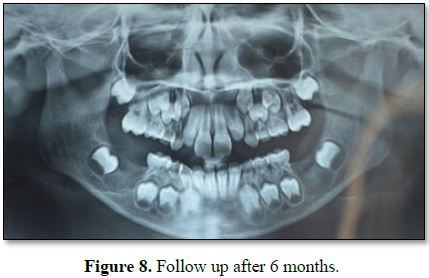

Patient was recalled after 6 months and no swelling or radiolucency was

present. But actual cause was still unknown (Figure 8).